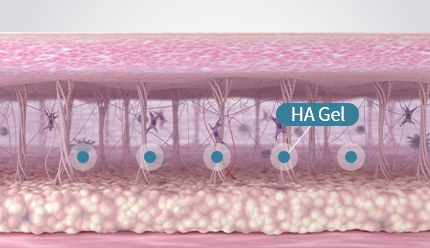

섬유아세포가 대사활동을 하는 동안 섬유아세포에 자극을 주어

콜라겐을 생성하거나, 콜라겐이 서로 합성되는 현상이 일어납니다.